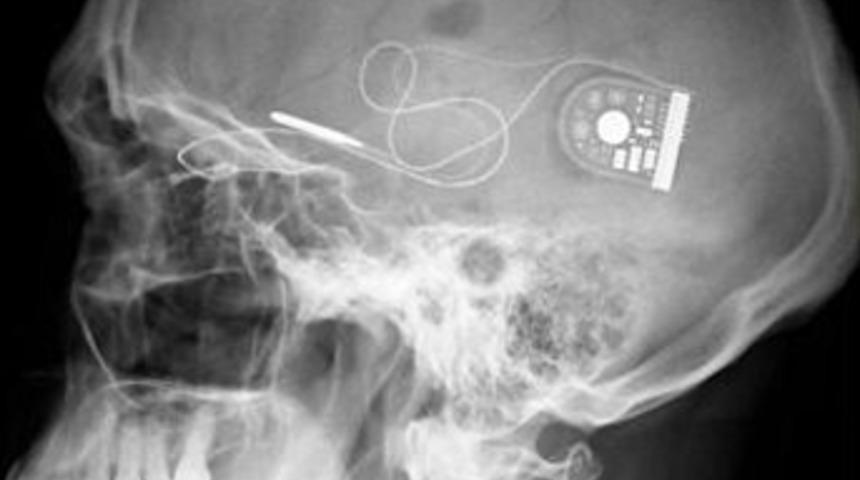

Bilim insanları görme bozukluğu olan dokuz insanın gözüne yerleştirdikleri mikroçiple yeniden görmesini sağladı. Bin 500 piksel ve 3 mm büyüklüğündeki mikroçip gözbebeğinin arkasına yerleştiriliyor.

Bilim insanları tarafından geliştirilen bir mikroçip dejeneratif hastalık geçirip kör olan dokuz kişinin yeniden görmesini sağladı. Hastalık geçiren insanların gözlerine yerleştirilen mikroçip kalıtsal retinitis pigmentoza'nın (RP) tedavi edilmesinde etkili olduğu belirtildi.

3 mm'lik çip bu durumdan muzdarip olan milyonlarca işnsan için önemli bir adım olduğu ifade edildi. Çok ince olan bu çip Alman Tubingen Üniversitesi uzmanları tarafından geliştirildi. Retinanın altına yerleştirilen çip optik dokulara elektrikle uyarı gönderiyor. Son denemelerde çoğu hasta kendilerine gösterilen yüz ifadelerini tanıdı. Hastalar masadaki meyve ve trafik sinyal levhaları gibi nesneleri birbirinden ayrımay başarabildi.

Tubingen Üniversitesi Göz Araştırmaları Enstitüsü'nden Prof. Eberhart Zrenner klinik çalışmaların beklentileri yükselttiğini söyledi. Zrenner, "Bu araştırma retina implant teknolojisinin geliştirilmesi için bize yardımcı olacak. Böylelikle retina bozulması yaşayan insanların harici görme gerecine ihtiyacı kalmayacak" dedi.

RP retinayı etkileyen ve yavaş yavaş körlüğe götüren bir hastalık. Almanya'daki Retina Implant AG'nin Yönetin Kurulu Başkanı Walter-G Wrobel, "Çalışmaların devamının milyonlarca insanın karanlıktan kurtulmasına yardımcı olacağını belirterek "36 hasta üzerinde çalışmalara devam ediyoruz. Onların iyi niyetle katılımı çığır açan bir çalışmaya öncülük edecek" dedi.